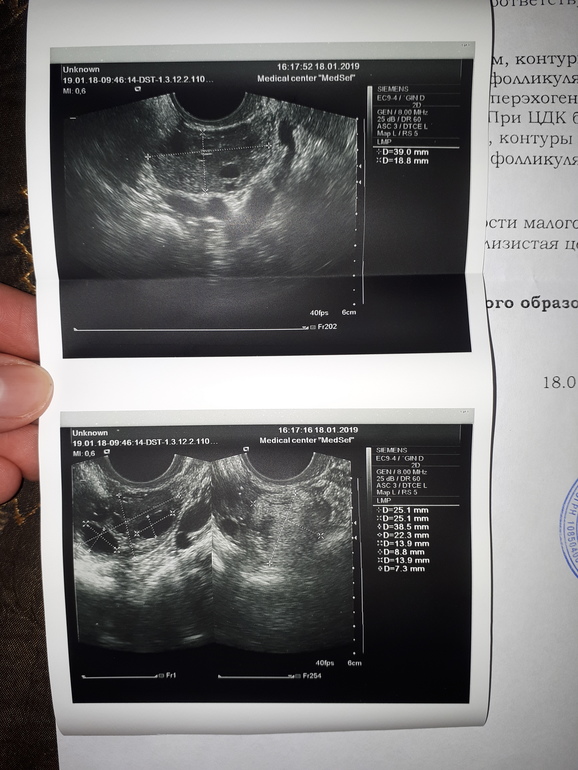

Сходила сейчас на узи. Врач вообще ничего не сказала. Все в порядке то?А то с мужем планируем ребенка,не хотелось бы столкнуться с неожиданными проблемами. Стоит ли сходить на фолликулометрию?Или туда,только если получаться не будет?

Вам надо идти к врачу. Вам же в заключении написали объемная тератома!!!! Надо либо исключить,либо подтвердить и лечить!